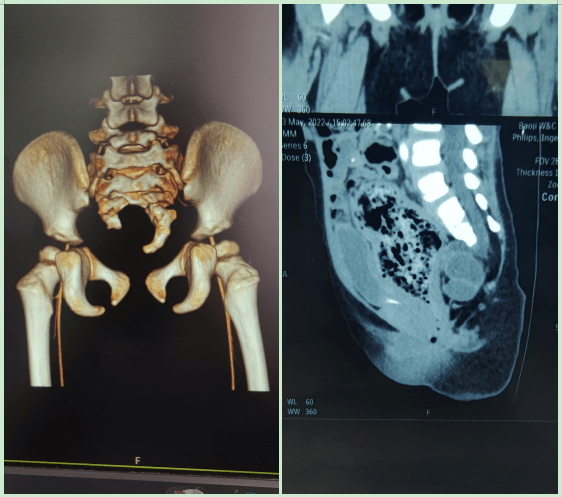

创伤性腰骶脱位伴高位骶骨骨折一例